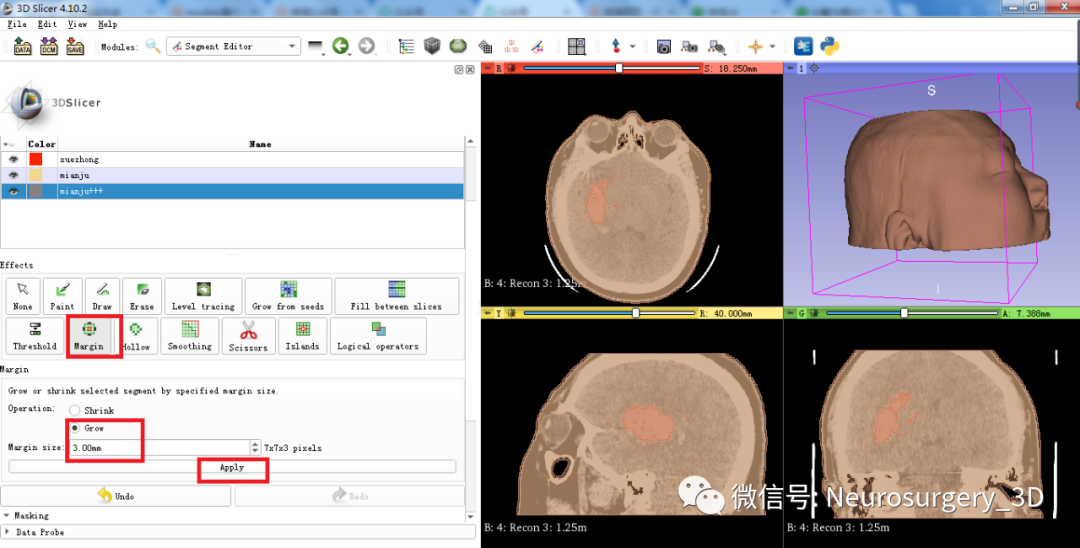

一)利用segment editor![]() Margin

Margin![]() 中的Grow和逻辑运算模块生成面具模型

中的Grow和逻辑运算模块生成面具模型

2、利用Margin![]() 中的Grow膨胀Mo xing_2,可见图中红褐色大于绿色模型。

中的Grow膨胀Mo xing_2,可见图中红褐色大于绿色模型。